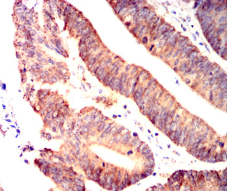

IRF3 Mouse Monoclonal antibody[5G3E2]

This gene encodes a member of the interferon regulatory transcription factor (IRF) family. The encoded protein is found in an inactive cytoplasmic form that upon serine/threonine phosphorylation forms a complex with CREBBP. This complex translocates to the nucleus and activates the transcription of interferons alpha and beta, as well as other interferon-induced genes. The protein plays an important role in the innate immune response against DNA and RNA viruses. Mutations in this gene are associated with Encephalopathy, acute, infection-induced, herpes-specific, 7.

IHC    1/200 - 1/1000